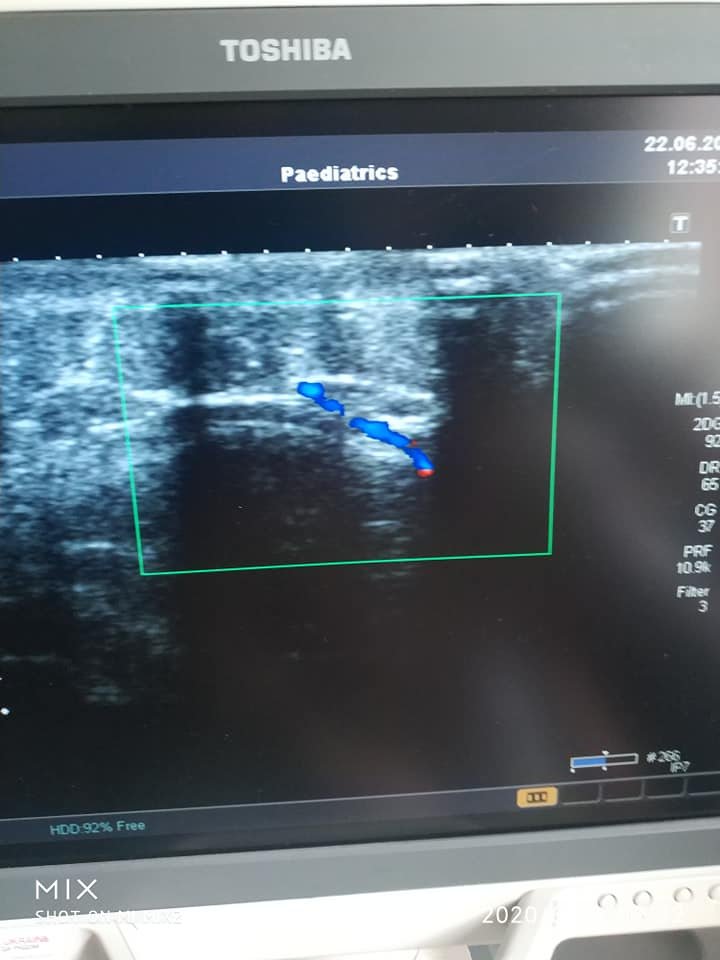

"Подросток последние пять лет борется со злокачественной опухолью. Мальчик прошел через все: химиотерапия, лучевая терапия, многочисленные операции и даже удаление глаза. К сожалению рана, после операции заживать не спешила. И на помощь ребенку пришли комбустиологи-микрохирурги. Несколько недель подготовки. Сложные дообследования, многочисленные переговоры и вот наконец операция. 2 бригады, каждая под руководством профессора. 7 часов операции под микроскопом. Долгие часы и дни ожидания, и наконец Павел Алексеевич говорит, что можно выдыхать. Лоскут жизнеспособный, рана закрыта и можно праздновать победу. Это была первая в нашей больнице (а скорее всего и в Украине) микрохирургия на пересадке сложного кожно-мышечного лоскута ребенку", - рассказал врач.